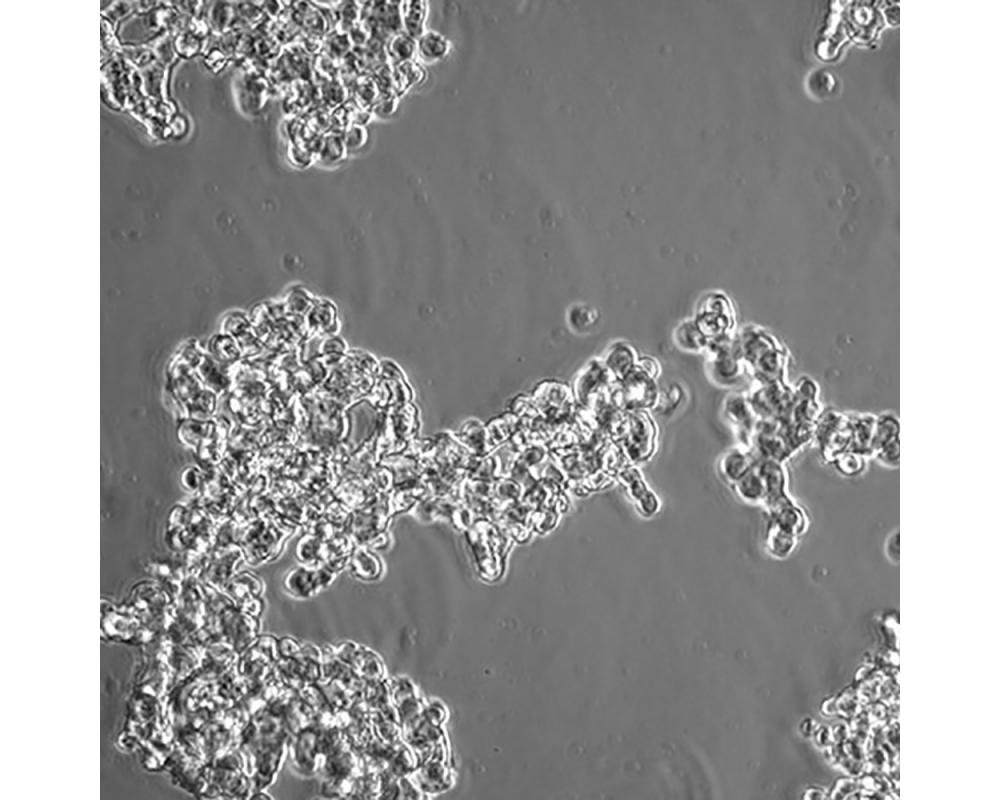

NCI-H526

產(chǎn)品名稱 NCI-H526

中文名稱 人小細(xì)胞肺癌細(xì)胞

組織來源 小細(xì)胞肺癌;骨髓轉(zhuǎn)移;男性

生長(zhǎng)特性 懸浮